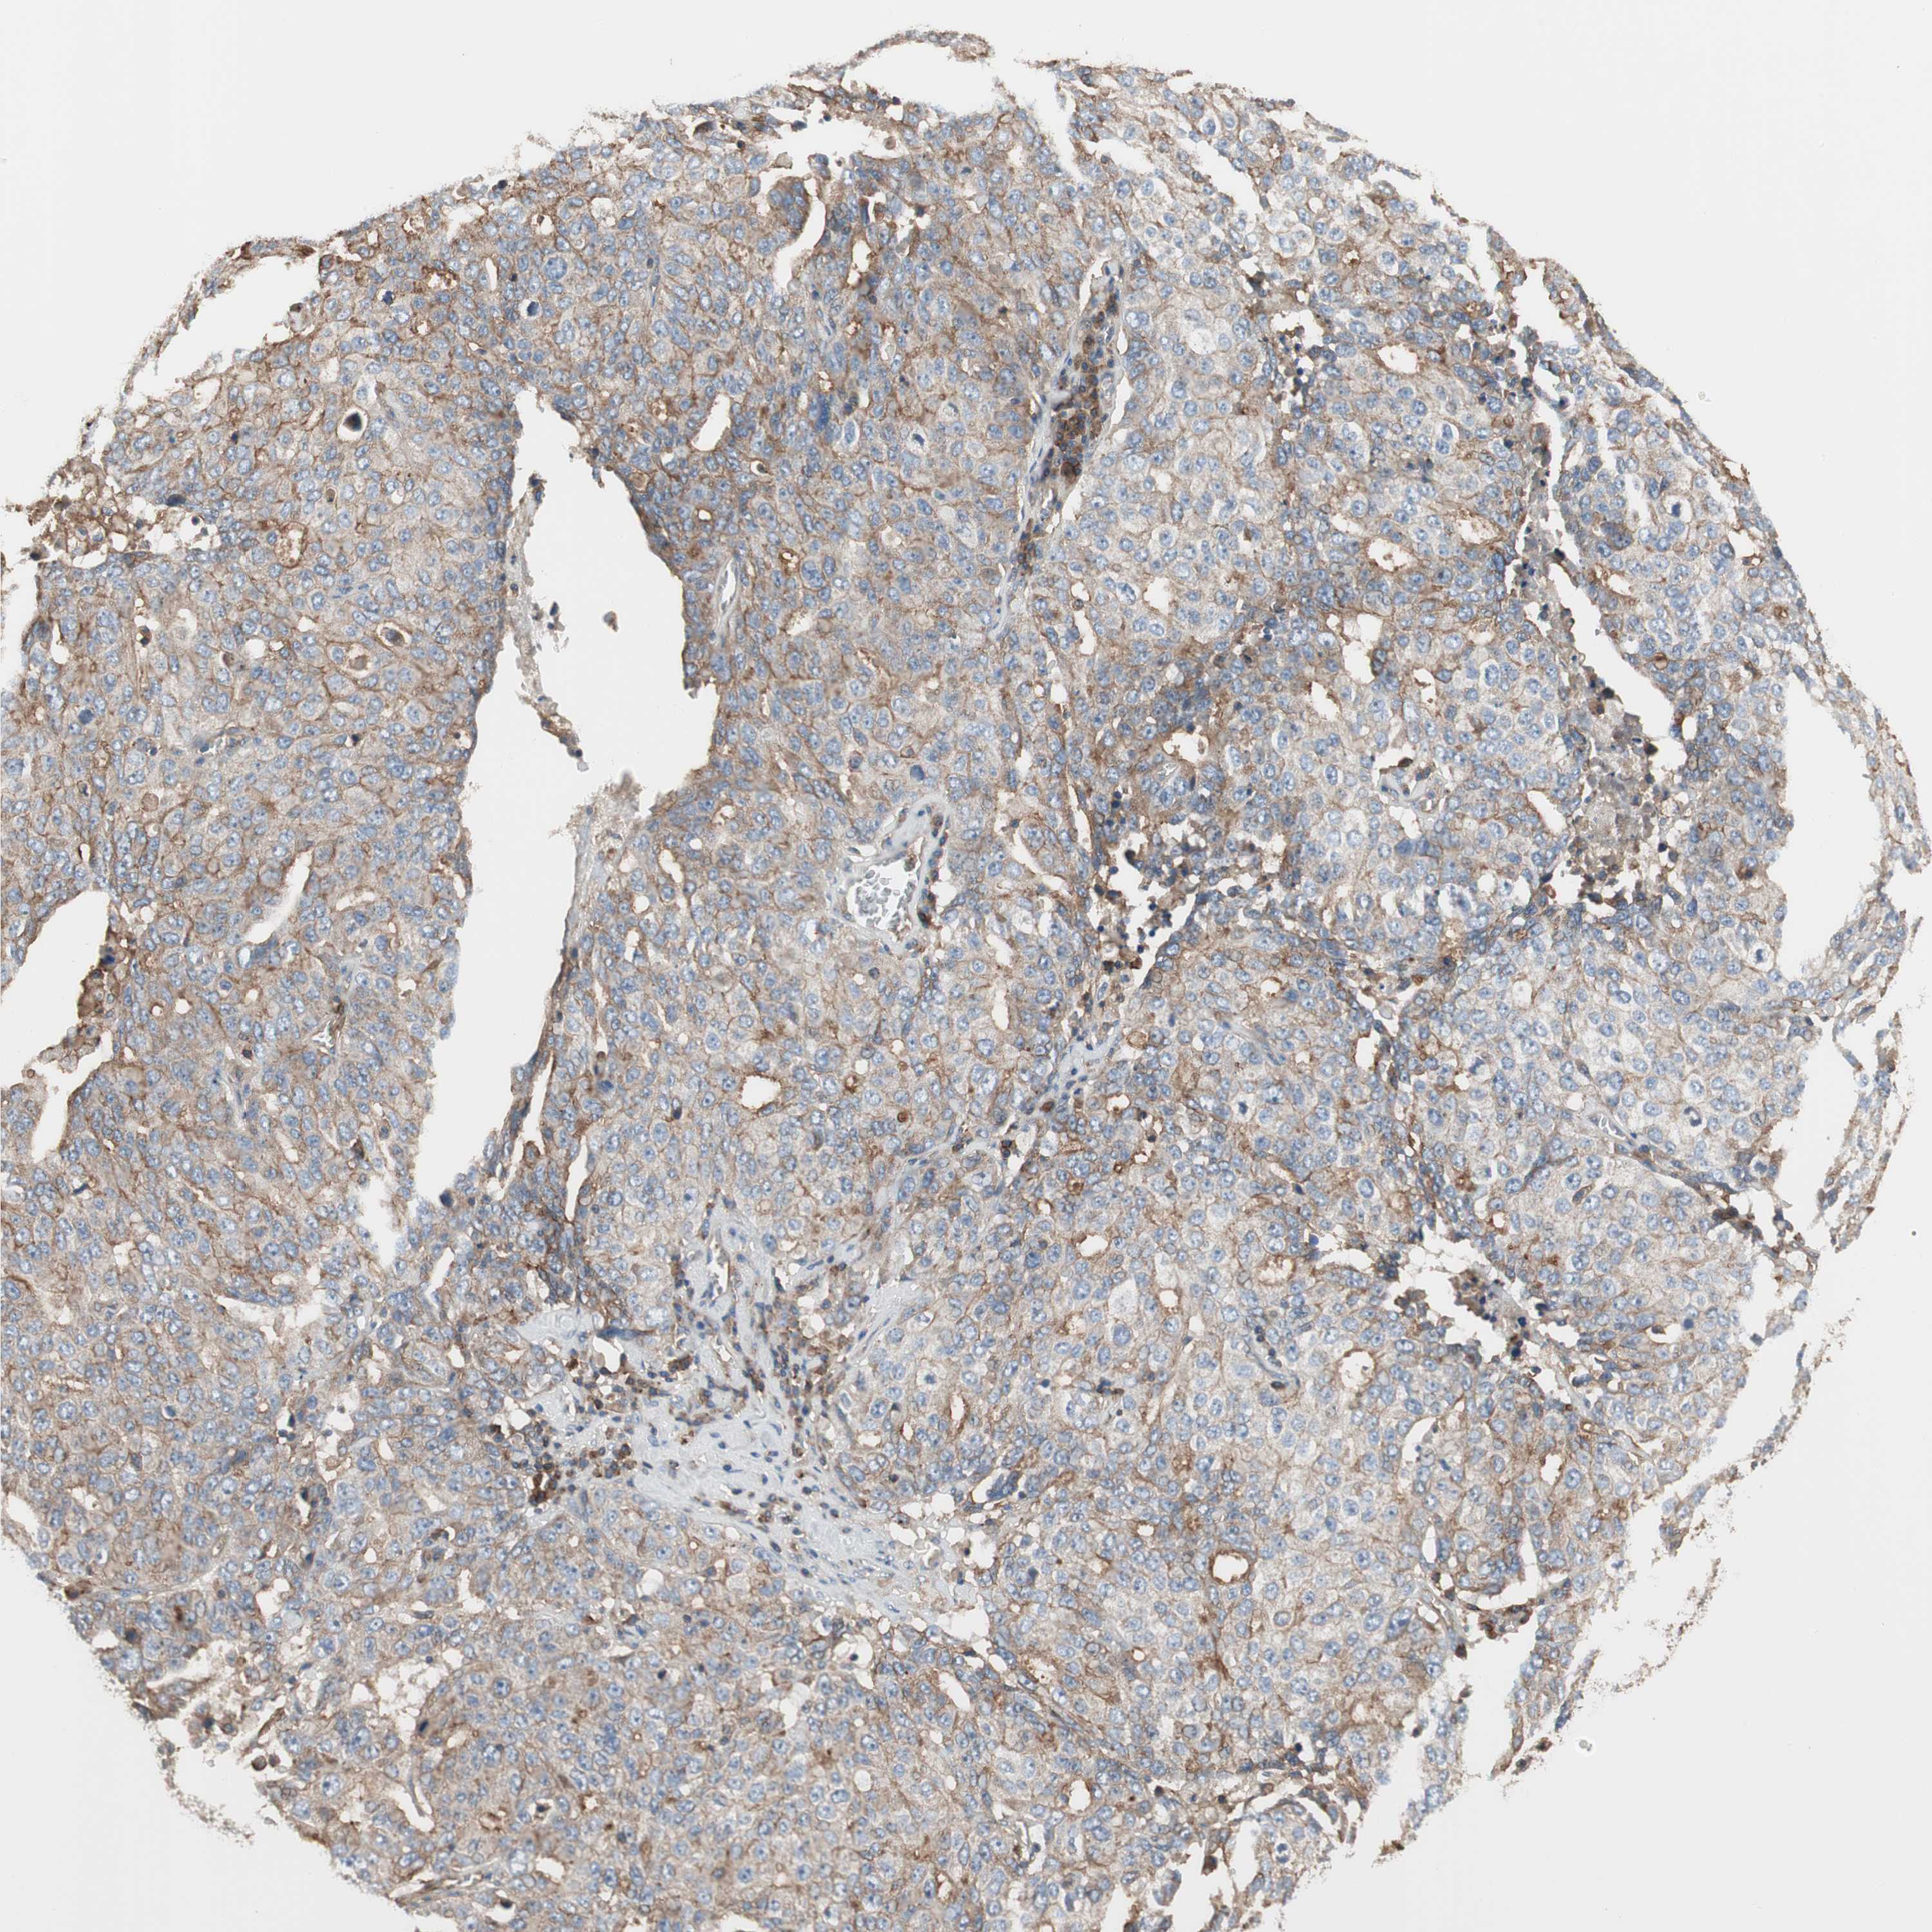

OVARIAN CANCER - Protein expressioni

A mouse-over function shows sample information and annotation data. Click on an image to view it in a full screen mode. Samples can be filtered based on level of antibody staining by selecting one or several of the following categories: high, medium, low and not detected. The assay and annotation is described here.

Note that samples used for immunohistochemistry by the Human Protein Atlas do not correspond to samples in the TCGA dataset.

Antibody stainingi

Antibody staining in the annotated cell types in the current human tissue is reported as not detected, low, medium, or high, based on conventional immunohistochemistry profiling in selected tissues. This score is based on the combination of the staining intensity and fraction of stained cells.

Each image is clickable and will lead to virtual microscopy that enables deeper exploration of all samples and also displays staining intensity scores, fraction scores and subcellular localization as well as patient and tissue information for each sample.

Antibody HPA007406

Antibody HPA007917

Cystadenocarcinoma, serous, NOS

Carcinoma, endometroid

Cystadenocarcinoma, mucinous, NOS

Carcinoma, NOS